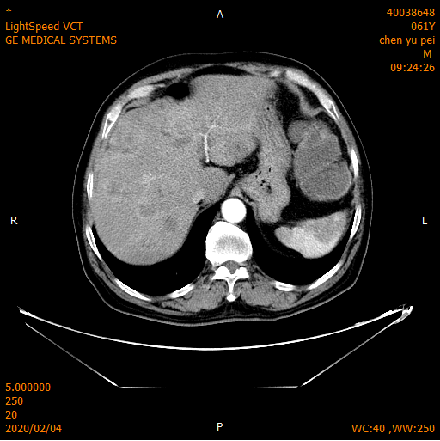

2020-02-04 CT

肝脏多发异常强化灶,考虑转移。

横结肠-降结肠交界处壁增厚强化,请结合消化道检查,腹腔部分肠管扩张积气积液,可见气液平,请结合临床。